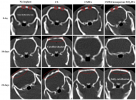

محققان دانشگاه صنعتی سهند موفق به توسعه داربستهای سهبعدی هیدروکسی آپاتیت-کیتوسان حاوی ذرات مزومتخلخل برای درمان و جایگزینی استخوانها شدند.